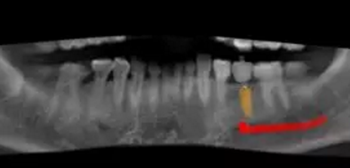

術(shù)前,導(dǎo)板設(shè)計(jì)工程師,根據(jù)CBCT以及模型數(shù)據(jù),將患者的解剖結(jié)構(gòu)、軟組織形態(tài)和修復(fù)效果數(shù)字化三維重建,在設(shè)計(jì)軟件內(nèi)進(jìn)行虛擬修復(fù)體冠設(shè)計(jì),同時(shí)與臨床醫(yī)生一起,根據(jù)#35牙槽骨高度以及寬度,結(jié)合下牙槽神經(jīng)管,設(shè)計(jì)好合適的種植位點(diǎn)。

根據(jù)上述植入和修復(fù)方案,立體設(shè)計(jì)Implant Guide™全程導(dǎo)板,鑒于下頜需避讓下頜神經(jīng)管,并考慮到種植體與頰舌側(cè)、近遠(yuǎn)中側(cè)的關(guān)系,設(shè)計(jì)在該牙位植入1顆Alpha-Bio Tec ICE 4.2x 10mm的植體。

術(shù)前術(shù)后CBCT數(shù)據(jù)對(duì)比分析,植體就位準(zhǔn)確。